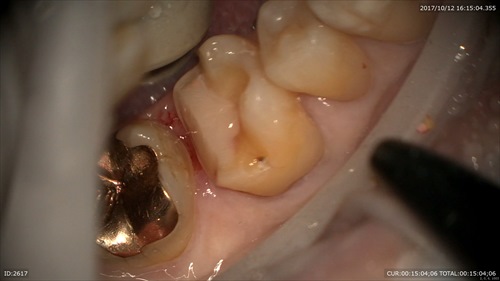

むし歯でなくなった部位を補強して。精密な型取り。とにかく丁寧に。

本日セットしました。段差などないかをマイクロスコープで確認します。

痛みがないと喜んで頂けました。ありがとうございます。